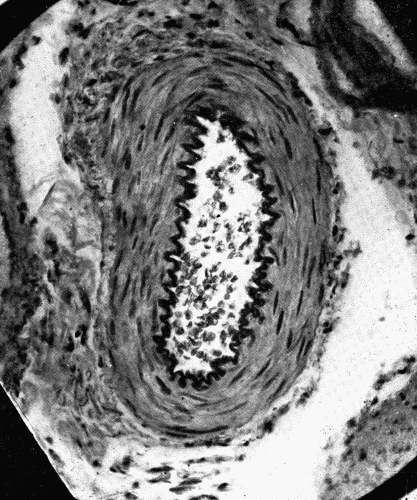

Fig. 1.—Cross section of a large artery showing the division into the three coats; intima,

media, adventitia. The intima is a thin line composed of endothelial cells. The

wavy elastic lamina is well seen. The thick middle coat is composed of muscle fibers

and fibroelastic tissue. The loose tissue on the outer (lower portion of cut) side of the

media is the adventitia. (Microphotograph, highly magnified.) Fig. 1.—Cross section of a large artery showing the division into the three coats; intima, media, adventitia. The intima is a thin line composed of endothelial cells. The wavy elastic lamina is well seen. The thick middle coat is composed of muscle fibers and fibroelastic tissue. The loose tissue on the outer (lower portion of cut) side of the media is the adventitia. (Microphotograph, highly magnified.)

The whole vascular system, including the heart, has an endothelial lining, which may constitute a distinct inner coat, the tunica intima, or may be without coverings, as in the case of the capillaries. The intima (Fig. 1) consists typically of endothelium, reinforced by a variable amount of fibroelastic tissue, in which the elastic fibers predominate. The tunica media is composed of intermingled bundles of elastic tissue, smooth muscle fibers, and some fibrous tissue. The adventitia or outer coat is exceedingly tough. It is[28] usually thinner than the media, and is composed of fibroelastic tissue. This division into three coats is, however, somewhat arbitrary, as in the larger arteries particularly it is difficult to discover any distinct separation into layers.